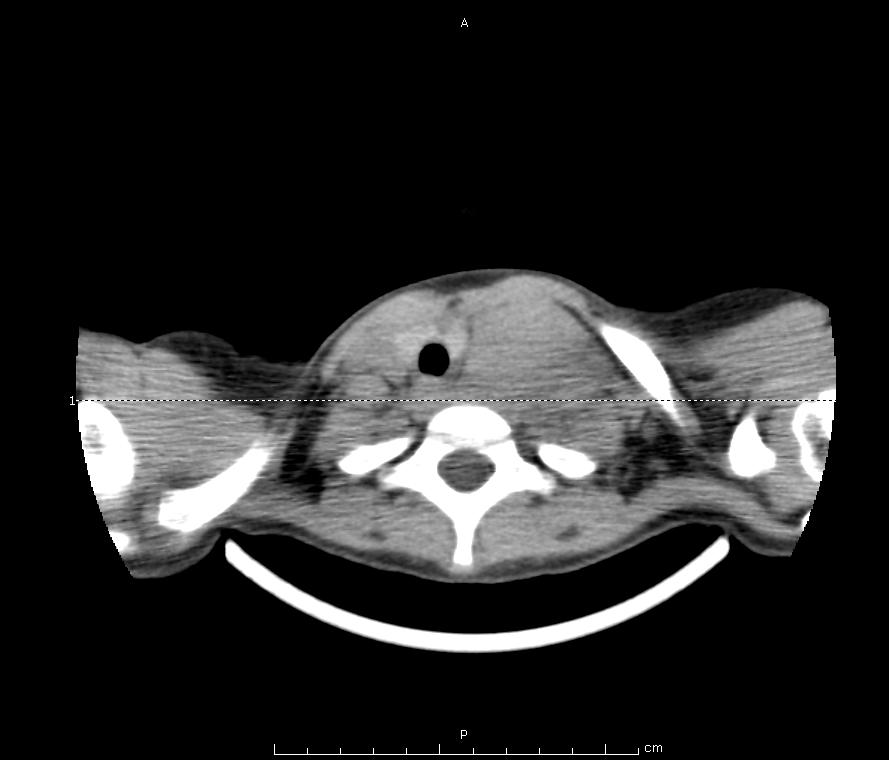

Nel sospetto di una neoformazione a livello del torace si esegue quindi una TC Torace con riscontro di voluminosa massa mediastinica anteriore, paramediana sx, estesa dalla regione laterocervicale inferiore sx fino in sede sovra diaframmatica (diam. Max AP-LL-CC 98X97X169 mm) (Figura 3 e Figura 4). Tale massa, che comprime alla base del collo il lobo sinistro della tiroide e disloca lateralmente l'asse tracheale e l'esofago senza segni di infiltrazione locale, avvolge completamente tutte le strutture vascolari presenti in ambito mediastinico che mantengono comunque una regolare perviet� endoluminale. Viene inoltre confermata la presenza di versamento pericardico e di versamento pleurico a sinistra associato ad atelettasia passiva del parenchima polmonare contiguo. Si esegue inoltre un'ecografia del collo che in sede laterocervicale e sovragiugulare sx apprezza la presenza di tessuto di tipo solido disomogeneo con diametri di circa 3,5x 2,4 cm che ingloba il fascio vascolare del collo e impronta il lobo sx della tiroide, nel cui interno si visualizzano alcuni linfonodi ipoecogeni. Gli altri esami eseguiti (TC Addome, TC Cranio-Encefalo) risultano negativi.Nel sospetto di un'origine linfomatosa, B. viene sottoposta in videotoracoscopia a biopsia della massa il cui successivo referto istologico conferma la diagnosi di Linfoma linfoblastico a precursori T. Viene quindi intrapresa la chemioterapia tuttora in corso.